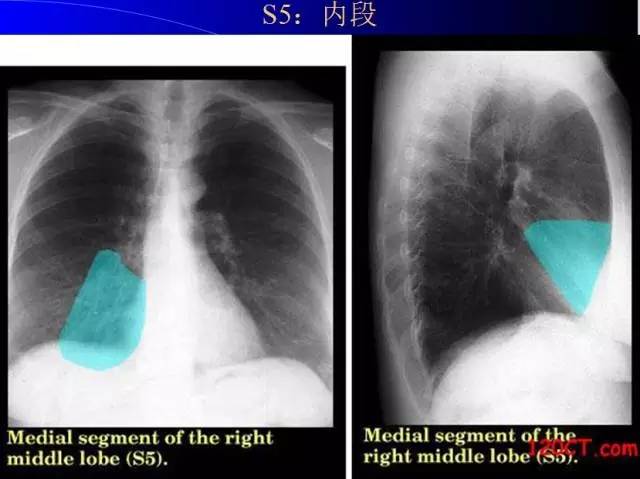

肺部基础X片及CT片解读